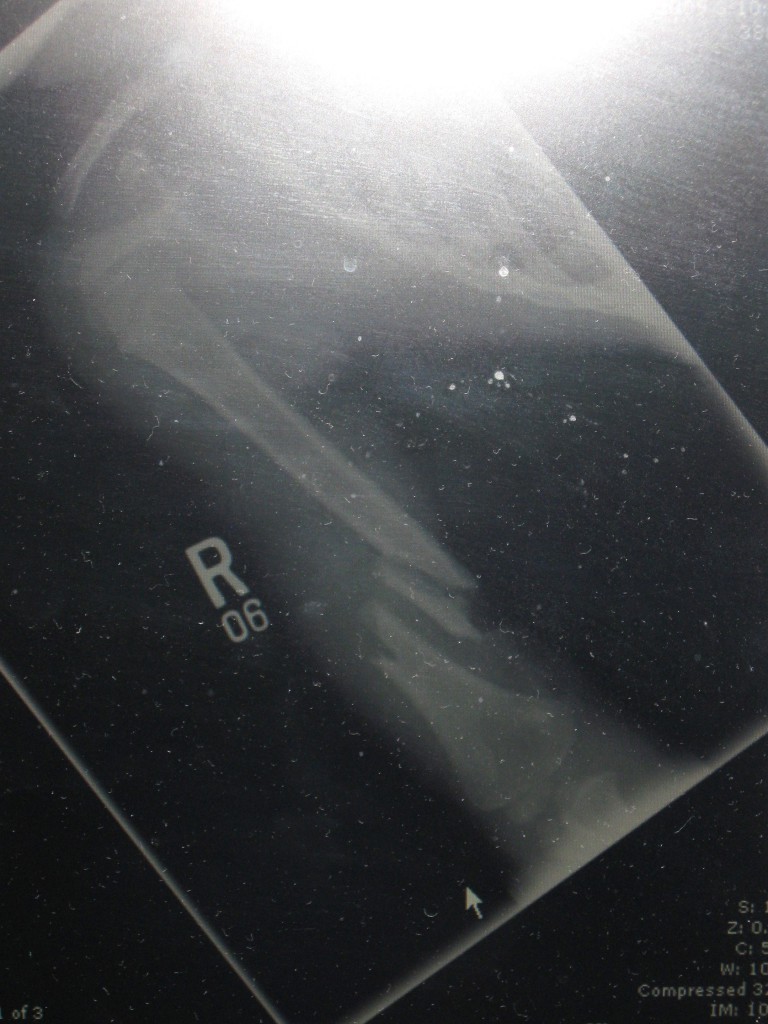

Arm and Elbow Fractures

When our son Quinn was four years old, we called Dr. Scher's office to describe his acute condition. It was Saturday of Columbus Day weekend, he was sick and injured and we urgently begged for someone at HSS to take over his care. As a patient, Quinn was completely unknown to the HSS staff. Despite that, the HSS team listened to us and believed that Quinn was unnecessarily suffering after a severe open fracture to his humerus had left him hospitalized for a week with unresolved symptoms, extreme pain and intermittent listlessness. Our situation sounded complicated: possibly surgically resetting a break, excessive infection, and other unknowns.

Due to poor initial attention, alarming aspects of Quinn's condition had been overlooked. For ten days, his body had been suffering from foreign body infection due to playground wood chips that were lodge in his arm from the original accident. He also had undiagnosed nerve damage that had destroyed all sensation in his arm and hand. After five surgeries and extensive rehabilitation at HSS, Quinn is not only a rock start in the classroom but also an actual rock climber on a local team. He still speaks of his doctors, knowing that their expertise and compassion gifted him full use of his hand and arm.